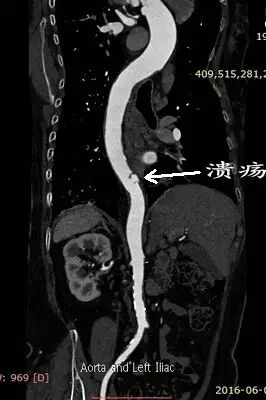

但术前的CTA评估又发现新的问题(图1、2),患者同时合并左侧锁骨下动脉的重度狭窄,狭窄>80%,平素血压多测量右上肢,并未发现,入院测量双上肢血压差别高达30mmHg!更困难的是,主动脉溃疡的破口位于胸10椎体部位,行覆膜支架腔内治疗,患者术后截瘫风险较大。患者病情危重,一旦主动脉破裂出血,死亡率极高!患者家属再次陷入恐慌,在此两难之际,王兵教授果断决策,手术要做,且决定同时介入治疗锁骨下动脉狭窄,因为锁骨下动脉狭窄的解除不仅能改善患者脑部及上肢供血,同时对脊髓供血起到良好的代偿作用,但即便如此,术前也与麻醉科胡强夫主任反复沟通,做好脑脊液穿刺引流准备,最大限度降低截瘫风险。

图2:主动脉透壁性溃疡

充分的术前评估及准备,确保了手术的顺利进行。术中王兵教授亲自主刀,崔文军副主任及王颖、司江涛主治医师作为助手,经股动脉小切口,先于左侧锁骨下动脉狭窄处准确定位后置入球扩支架1枚,再次造影明确溃疡位置后,将主动脉带膜支架顺利输送到位,并成功释放,完全覆盖病变主动脉,复查造影效果满意(图3)。术后患者即清醒,安全返回病房,测量双上肢血压无差别,双下肢温度、颜色正常,感觉及运动均无异常,即挽救了患者生命,也成功避免了截瘫的发生,大家悬着的心都放了下来。术后施敏护士长带领的护理团队,娴熟而全面的护理确保患者平稳度过围手术期,术后10天复查CTA:左侧锁骨下动脉及主动脉支架均位置良好,形态满意。目前李大娘已顺利康复出院。